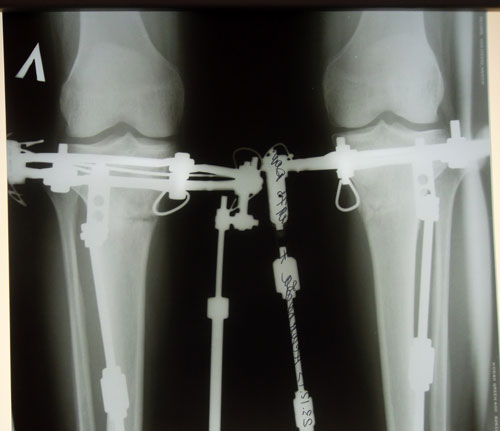

- Диагноз: О-образная деформация ног